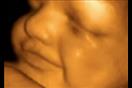

يزن الطفل حوالي 10 أونصات، ويبلغ طوله أكثر بقليل من 6 بوصات، وخلال تلك المرحلة، يعلو الرحم إلى مستوى السرة، ويمكن للطفل أن يمص إبهامه، ويتثاءب، ويتمدد.

وإذا لم تكن الأم قد شعرت بحركة الجنين داخلها في المراحل السابقة، فبنسبة كبيرة ستشعر بها خلال تلك المرحلة.

وعادة ما يتم إجراء فحص الموجات فوق الصوتية لجميع النساء الحوامل في الأسبوع "20"، ومن خلاله يتأكد الطبيب من أن المشيمة سليمة ومتصلة بشكل طبيعي، وأن الطفل ينمو بشكل صحيح، كما يمكن التعرف على نبضات قلب الطفل وحركة جسمه وذراعيه وساقيه، وعادةً ما يمكن معرفة جنس الجنين.